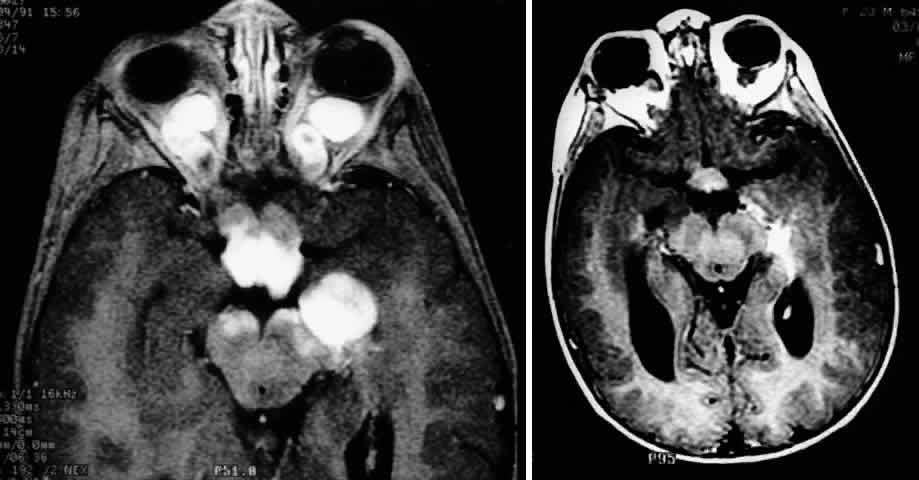

Fig. 2. Contrast-enhanced T1-weighted axial MRI of the orbits of the patient in Figure 1, demonstrating a large optic pathway glioma with posterior extension into the optic tracts and radiations. (Courtesy of Orlando Ortiz, MD, and Jeffrey Hogg, MD)

The use of chemotherapy for optic gliomas was prompted by the reported toxicity of radiation to the developing nervous system. Children irradiated before age 5 may have a tendency to incur behavioral and cognitive impairment.122 Results of chemotherapy for optic gliomas are difficult to interpret because of the sometimes indolent nature of these lesions, variably reported study follow-up periods, and small sample sizes. It does appear, however, that chemotherapy can effectively postpone radiation122 (Fig. 11 A and B). Unfortunately, there is little evidence that chemotherapy can provide long-term control of these tumors.20,122 In one series, approximately 60% of children treated for gliomas of the hypothalamus and optic pathways eventually had a relapse.122

Fig. 11. MRI scans demonstrating optic pathway glioma in a 14-month-old child with neurofibromatosis type 1, who presented with irritability and bilateral visual loss. The patient was treated with two courses of carboplatin and vincristine, resulting in marked visual recovery and a reduction in tumor size. Compare pretreatment MRI scan (A) with post-treatment MRI performed 5 months later (B). (Courtesy of Russell W. Walker, MD)